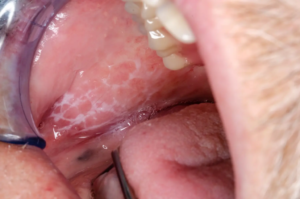

口腔扁平苔癬

口腔扁平苔癬は、口の中の皮膚や粘膜にできる炎症性の角化性病変です。

頬の内側や舌、唇などに白くて細長い線が網目状に現れるのが特徴で、びらんや潰瘍ができることもあります。

原因としては、歯科用金属のアレルギーや遺伝的素因、ストレスなどが関与していると考えられていますが、発症メカニズムはまだ十分に解明されていません。